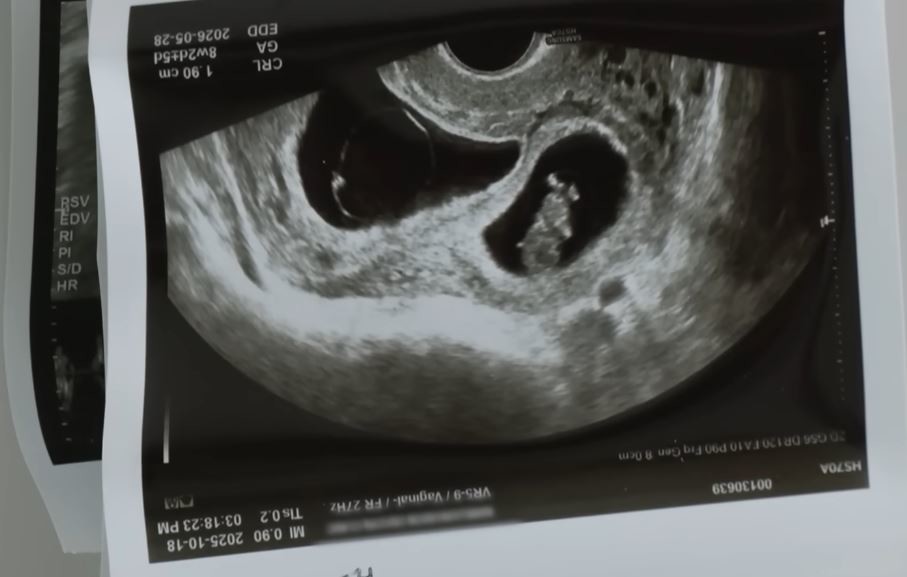

◆ 뱃속 아기들만이 버팀목이 된 만삭 아내의 호소

남편을 잃은 쌍둥이 임산부 A씨는 지난 10일 '음주운전에 대한 감형 없는 처벌법 제정에 관한 청원'이라는 제목의 글을 게재했다. A씨의 남편은 지난달 7일 만취 상태의 50대 남성 가해자가 운전한 SUV에 인도로 돌진당해 사망하는 비극을 겪었다. 가해자는 만취 상태로 운전대를 잡고 인도로 돌진하여 A씨 남편을 들이받았고 남편은 심정지 상태로 병원에 옮겨졌으나 끝내 숨졌다. A씨는 청원 글에서 남편과 자신이 한 번의 유산을 겪은 후 간절히 기다리던 쌍둥이 아기를 품에 안을 준비를 하던 참이었다고 비통한 심정을 토로했다.

A씨는 "저보다 더 기뻐하고 설레하며 행복이 두 배라고 매일 웃던 남편 모습이 아직도 눈에 선하다"고 밝혀 슬픔을 더했다. 이어 남편이 아직도 곁에 있는 것 같은 착각 속에서 허공에 울부짖는 자신을 붙잡아주는 것은 뱃속의 아기들뿐이라고 절규했다. 이처럼 예기치 않은 사고로 인해 한 가정의 행복이 송두리째 파괴된 상황에 국민들은 깊은 공감을 표하고 있다.